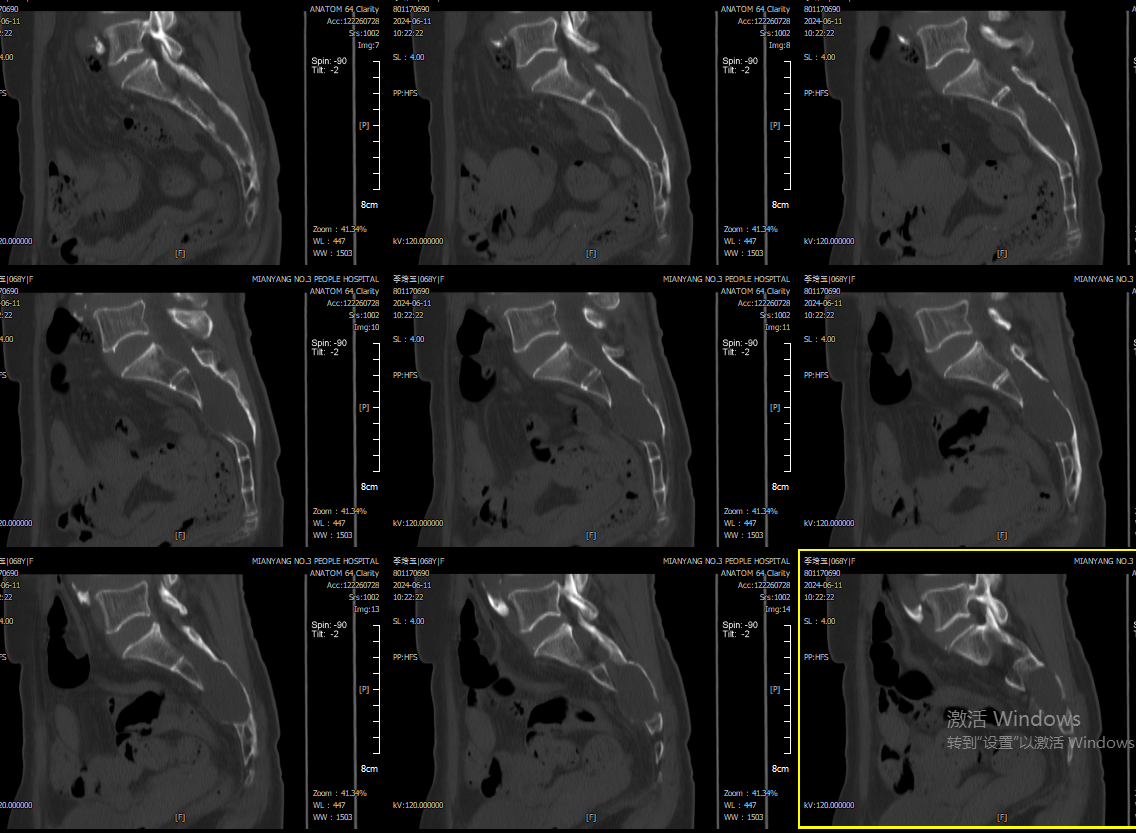

(术前CT可见囊肿巨大,已明显压迫破坏周围骨质)